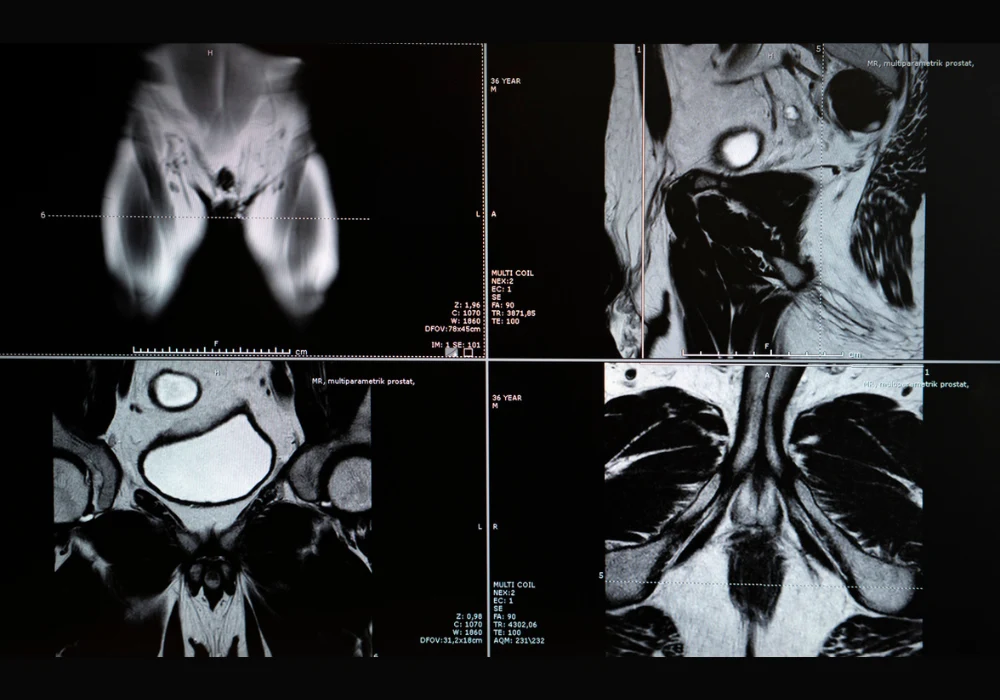

Prostate cancer remains one of the most prevalent malignancies affecting men worldwide and poses a major burden on health systems. While biparametric MRI is recommended as a primary diagnostic approach, its standard assessment method—PI-RADS—has limitations, particularly a high false-positive rate. These limitations often result in unnecessary biopsies, with implications for patient safety and resource utilisation. To address this, a multimodal machine learning model was developed and validated across multiple centres to improve the prediction of clinically significant prostate cancer using imaging, clinical and radiomic features.

The multimodal model was trained using retrospective data from twelve clinical centres, incorporating T2-weighted, diffusion-weighted imaging and apparent diffusion coefficient sequences. It combined radiomic features, which quantify shape and texture, with clinical variables such as age, PSA levels, lesion location and PI-RADS scores. Radiomic extraction covered the entire prostate gland using segmentation masks generated by a deep learning model. Performance was assessed through retrospective and prospective datasets, ensuring temporal generalisability and robustness across scanner vendors and field strengths.

Sensitivity analysis demonstrated that performance depended heavily on the diversity of training data. Models trained on single-vendor datasets showed reduced generalisability, underscoring the importance of multicentric training. Scanner vendor and the presence or absence of an endorectal coil were considered in model variants, confirming the added value of multimodal training. Sequence-specific performance highlighted the superiority of biparametric MRI combinations over individual sequences alone.